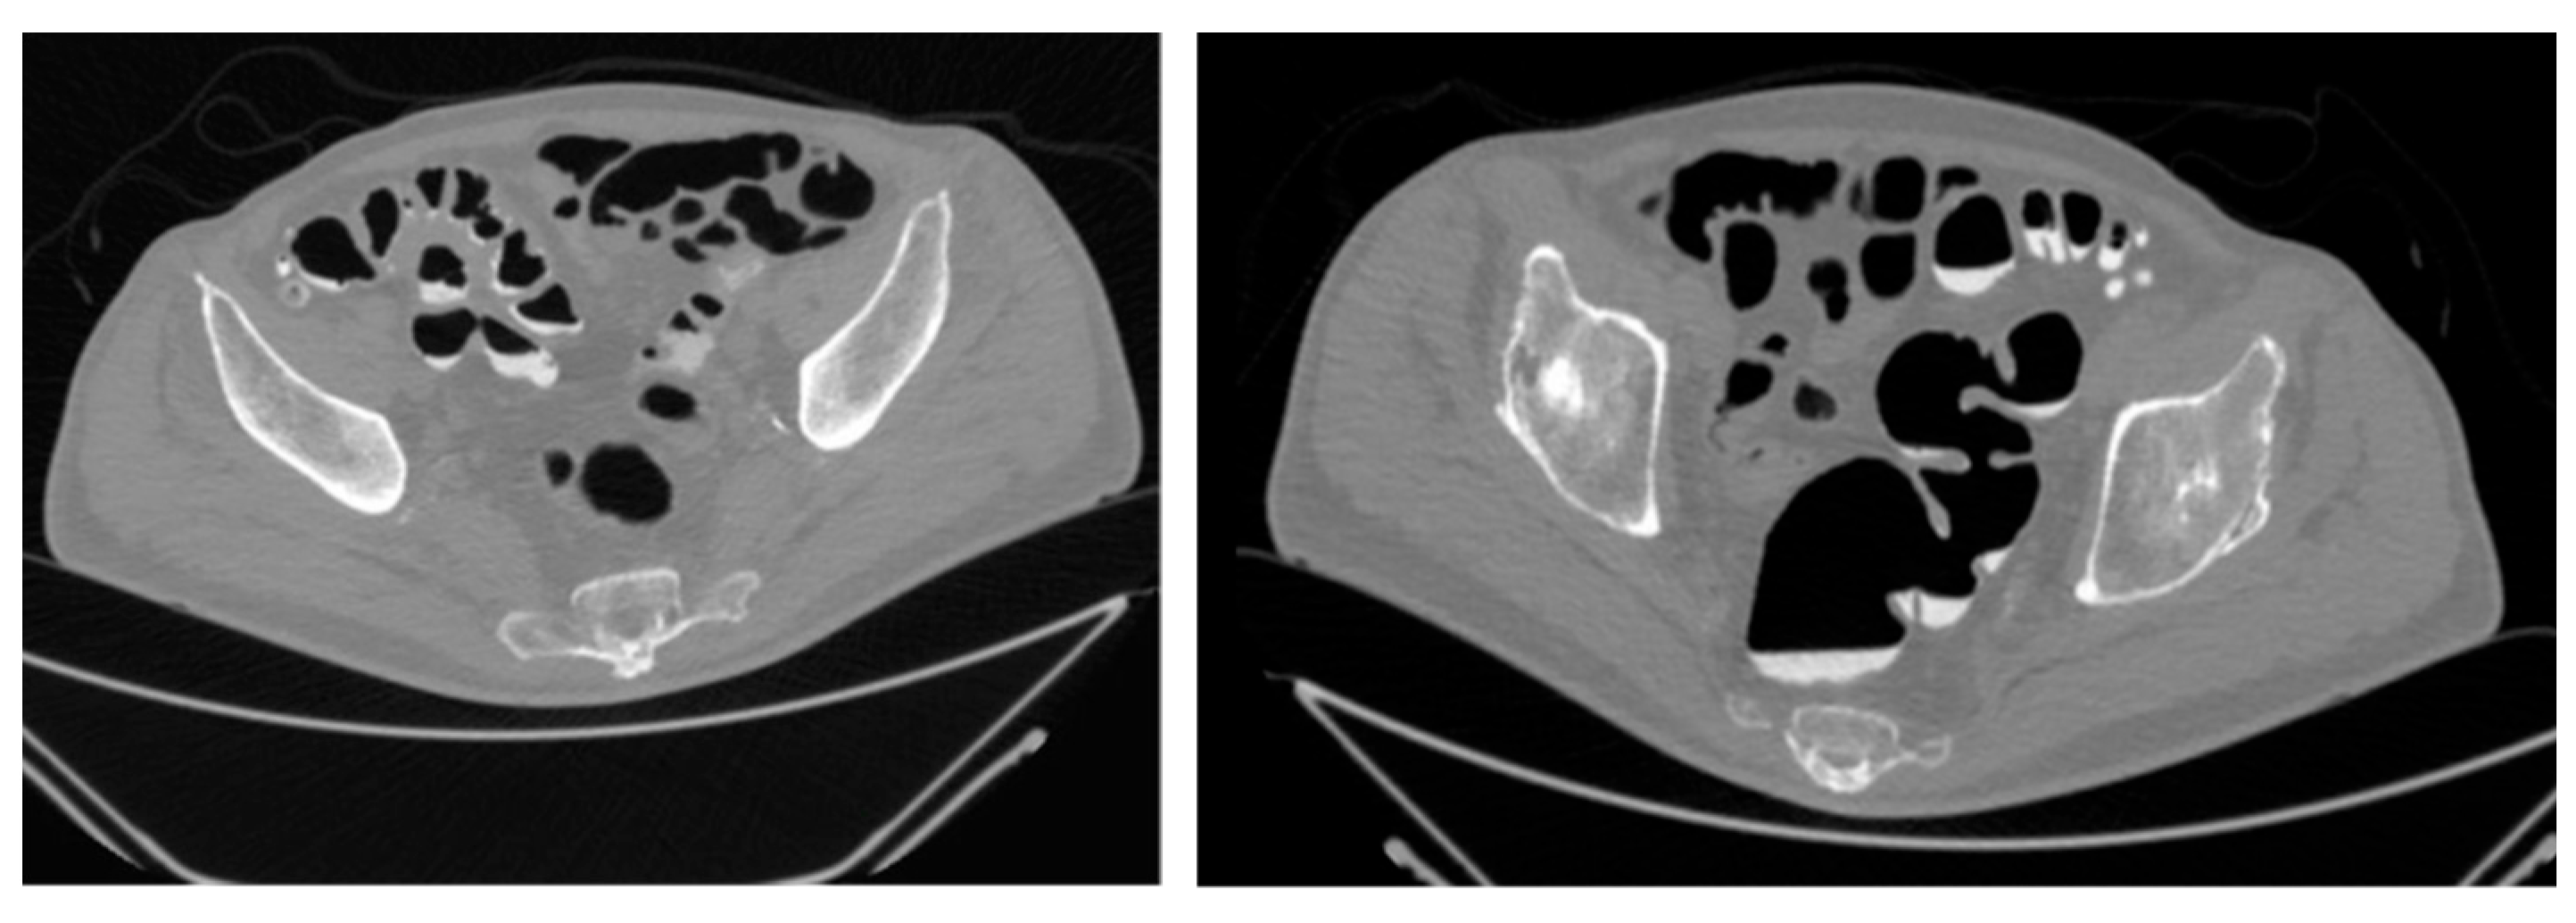

| Extent of diverticulosis | Massive diverticulosis of sigmoid and descending colon | Same finding confirmed with clearer visualization of segmental involvement |

| Stenotic area | Suspected narrowing, poorly defined | Stenotic segment clearly delineated, with precise localization and extension |

| Anatomical relationships | Limited perception of spatial relations | Improved understanding of relationship between diseased colon and surrounding structures |

| Surgical planning implications | Suggestive of need for resection | Supported decision for left hemicolectomy |

| Tactile/spatial perception | 2D visualization only | Physical 3D model provided tactile and spatial feedback useful for team discussion and planning |